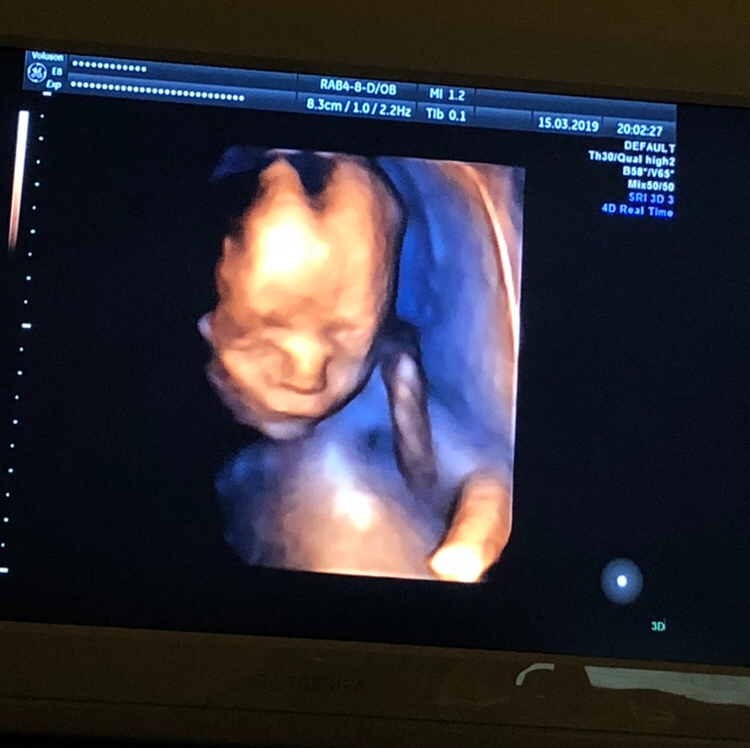

20 недель,2-ой скрининг,фото 3D

Результаты: УЗИ, КТГ, доплера, скринингаВчера было ровно 20 недель,2 скрининг,посмотрела как он вырос,такой хорошенький,палец сосал)) весит 350 гр. Все у него хорошо ттт. Хоть тут многие и говорили,что в 13 недель это рано для определения пола,но я считаю что нет,все зависит от врача,вчера специально даже спросила ее ошибалась ли она на сроке 13 недель с полом(первого,второго и этого третьего езжу только к ней скрининги делать), сказала,что с 13 недель она ни разу не ошибалась,что с такого срока уже все понятно. Вчера только подтвердила,что это ещё один мальчик😂. В спб она одна из лучших узи специалистов и кто скрининги делает идеально. Вдруг кому понадобится фамилия ее Лисина,работает в роддоме на фурштатской. Малыш вчера идеально лежал,шевелился во всю,показывая себя во всей красе и во всех ракурсах,видимо хотел угодить отцу,который тоже приехал посмотреть)) И фото мне на память,на ББ всегда проще зайти и посмотреть фото,чем потом искать их дома)) 😄😄